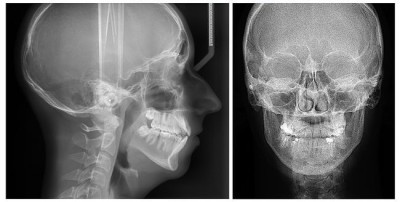

Далее лаборантом выполняются снимки: в зависимости от клинической ситуации и цели обследования могут быть задействованы разные проекции:

При рентгенографии костной структуры носа обязательными являются три проекции: прямая, правая и левая боковые. При наличии костных обломков может быть назначен еще один снимок в носо-подбородочной проекции.

- Рентген пазух носа часто делают в двух проекциях: затылочно-подбородной и затылочно-лобной. При необходимости может быть сделан снимок конкретной пазухи.

Рентгенологическое исследование костной структуры носа

При расшифровке рентген снимка костной структуры носа берется во внимание форма и дефекты строения костей. При выявлении трещин или переломов определяется их точная локализация, размеры, направление. Если есть костные обломки: указывается их локализация относительно костей или мягких тканей. По аналогичной схеме оцениваются инородные тела, обнаруженные на снимке и дефекты структур костной ткани (увеличение ее плотности или резорбция, новообразования).